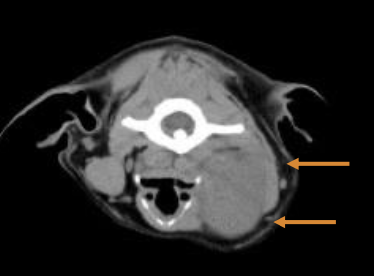

Imaging of oral cavity (CT preferred over skull radiographs)

What diagnostics can be used to stage OMM?

CBC, serum chemistry

LN cytology - even if normal in size (40% have LN mets)

Thoracic imaging - CT or 3v rads

Local imaging of mass - CT of head, planning of sx and/r RT